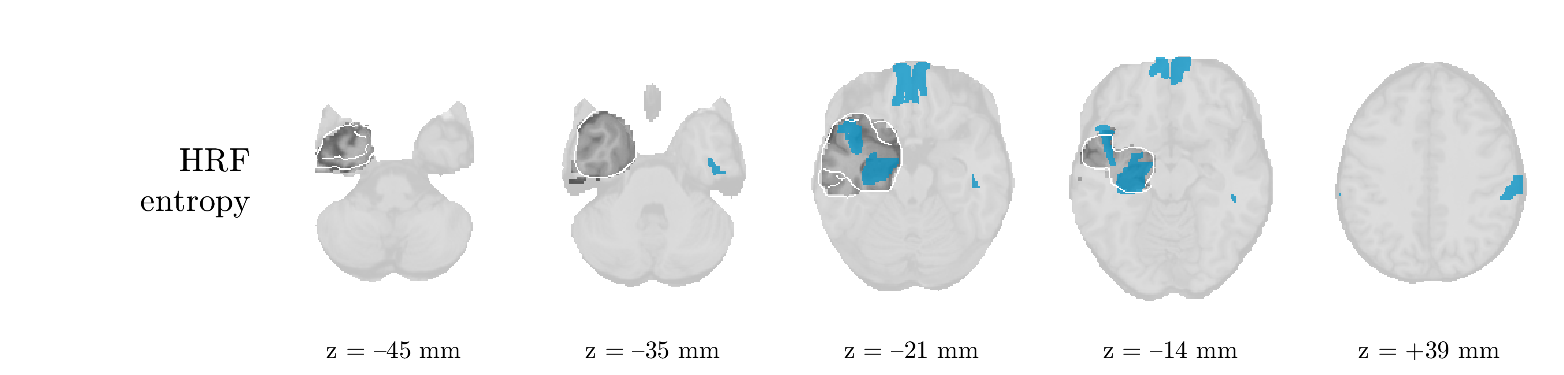

Patient 1

We analyze the solution with sources. Figure 1 shows the EEG signatures and HRF waveforms. One of the sources is highly correlated to the MWF reference (in grey), which was already known from Table B.3. This IED-related source had a typical low-frequency spectrum, which is expected for the typical spike-and-wave interictal discharges. The topography is relatively diffuse, although the highest amplitudes are mostly in the left hemisphere. This is in accordance with the lateralization of ictal onset zone (left temporal lobe, cfr. Table 1). There are some noteworthy observations to be made about some of the other components. The fourth has an unusually sharp spectrum, is mainly localized on two nonadjacent center electrodes, and is sustained for a single period of many seconds Hence, this component likely captured an artifact (of yet unknown origin), although we spotted no large-amplitude changes in the EEG itself. Similarly, the third source is only present at one frontal electrode, and exists in a frequency range above 20 Hz. It might represent a muscle artifact, e.g., due to frowning or twitching of some muscles in the forehead. The HRFs of all ROIs are shown in Figure 1(b). Two of the basis functions seem to have converged to a very similar waveform, which is an unfortunate possibility if two initial HRFs are too close to the same local optimum in their respective parameters. This reduces the expressive power of the basis set, which is clearly visible, since many ROIs have a nearly identical HRF. One of the twenty ROIs with the highest-entropy HRF overlapped the IOZ, although clearly this HRF (bold line) is not among the most dissimilar waveforms for this patient. This is also visible in Figure 2: both the HRF entropy and extremity maps show a small overlap with the delineated IOZ. Despite the good correspondence in the EEG domain, no significant (de)activation of the IED-component is found inside the IOZ.